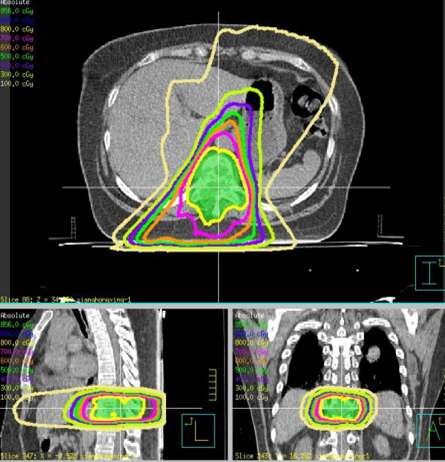

患者赵xx,女,42岁,MR:右侧髋臼窝及坐骨内异常信号,邻近肌肉及股骨小转子区域不同程度受侵。CT:右肺下叶见片状高密度影,气管及主支气管开口通畅,纵隔见结节状软组织影,较大者短径为13mm。右侧坐骨及右侧髋臼密度减低,形态欠规整。临床诊断:右肺下叶腺癌(cT2N2M1 Ⅳ期),纵隔淋巴结转移,多发骨转移。患者腰骶部疼痛明显,疼痛致活动受限,轮椅推入病房。2016年6月给予姑息减症放疗,靶区包括右侧骨盆转移灶(右股骨上段、右坐骨、右耻骨、右髂骨后段),6MV-X线调强放疗,单次量4Gy,放疗组织剂量24Gy/6次/8天。放疗后患者疼痛缓解,现行动自如。

患者项xx,女,60岁,因咳嗽伴腰骶部疼痛2个月,加重1周入院。核磁:胸10椎体及附件转移继发椎管狭窄,脊髓受压;寰椎侧块膨大伴异常信号,不除外转移。临床诊断:左肺下叶腺癌(cT4N3M1,IV期),侵及降主动脉,双侧纵隔淋巴结转移,椎体转移,双肺炎,肝硬化-代偿期,高血压病3级(极高危险组),上消化道出血。患者骨痛剧烈,平车推入病房。2017年4月给予姑息减症放疗,靶区PTV1为胸10椎体及附件, 6MV-X线调强放疗,单次量8Gy,放疗组织剂量8Gy/1次/1天。放疗后疼痛缓解,现行动自如,靶向治疗中。